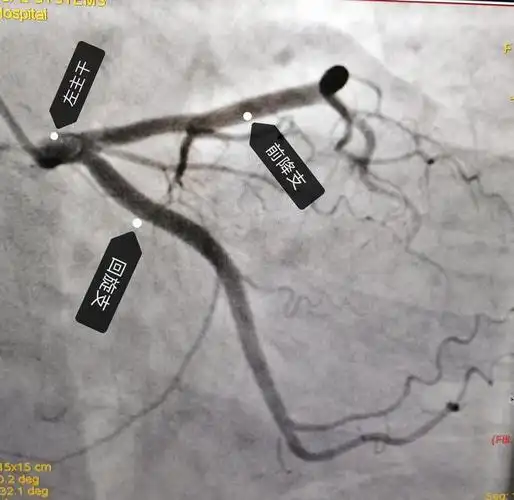

冠状动脉狭窄的血管造影

动脉冠状造影

冠脉造影影像解读